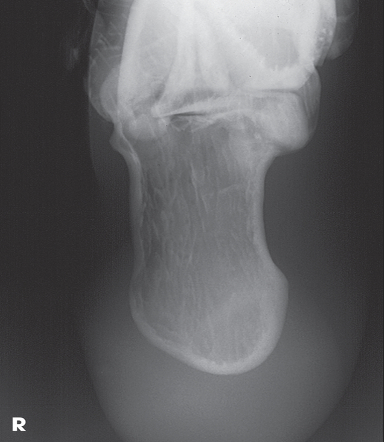

Name this projection.

Axial calcaneus

If the patient is supine, what type of projection is it?

Plantodorsal

How is the CR directed?

40 degrees cephalic (toward heel)

Where does the CR enter?

Plantar surface near 3rd metatarsal base

What anatomy is in profile?

Sustentaculum tali

What joints are seen?

Calcaneocuboid, talocalcaneal (subtalar)

What type of projection is used when the patient is prone?

Dorsoplantar